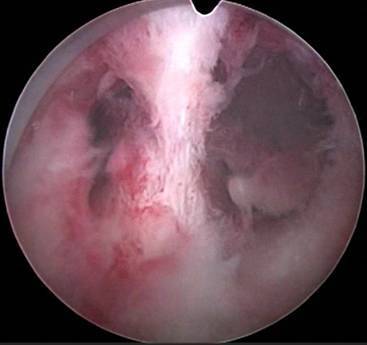

图1.5 宫腔镜下见子宫宫腔粘连